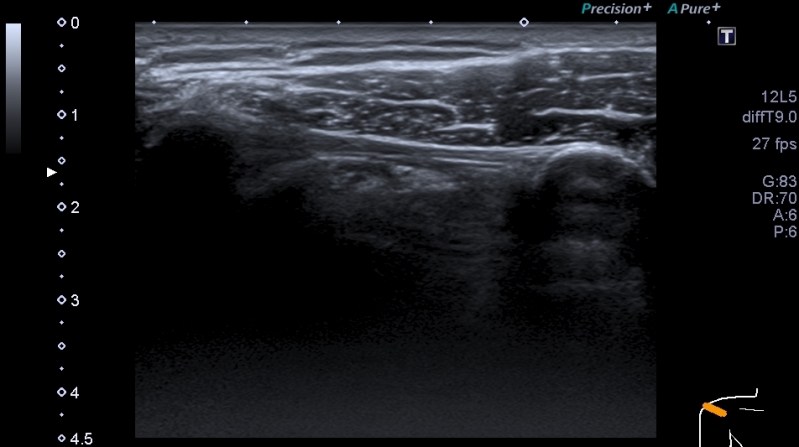

La banda oscura que está numerada con el 3 es el Ligamento Coracoacromial, que une el 1 y el 2 que son acromion y coracoides respectivamente. Conoces la anatomía, la inserción y todo lo básico de este ligamento, mira su aspecto ecográfico:

Ecográficamente es una estructura ligeramente hiperecogénica con respecto al músculo deltoides, marcada con líneas amarillas. En la inserción se abre como para abrazarse al hueso donde se inserta. Puedes ver con una buena sonda las lineas hipercogenicas alargadas en sentido de la inserción.

Técnicamente fácil no es, no te voy a engañar, aunque no es de los más complejos, la ecoestructura es muy variable, en función de cada anatomía, de como transmita el paciente y de la patología que afecte a la articulación…Tienes que poner el transductor un poco oblicuo en la línea imaginaria que une el acromion con la coracoides y angular milimétricamente para poder ver este ligamento con sus dos inserciones en el mismo plano como ves en las imágenes que te muestro. Te pongo la referencia anatómica de las ecoestructuras importantes las otras dos, son para que observes como debe verse.

El eje corto es más difícil, el ligamento es pequeño y planito…te lo señala la flecha amarilla, se observa con dificultad el recorrido si no los haces en vivo…Te lo muestro también para terminar este post con la anatomía cercana. Observa en este plano la relación entre el Tendón del Supraespinoso, la Bursa y el ligamento citado.